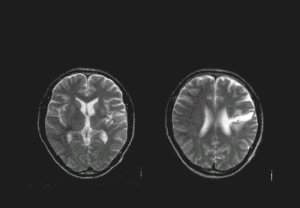

後方限局

後方限局病巣例

前方限局

前方限局病巣例

MCA広範病巣

広範病巣例